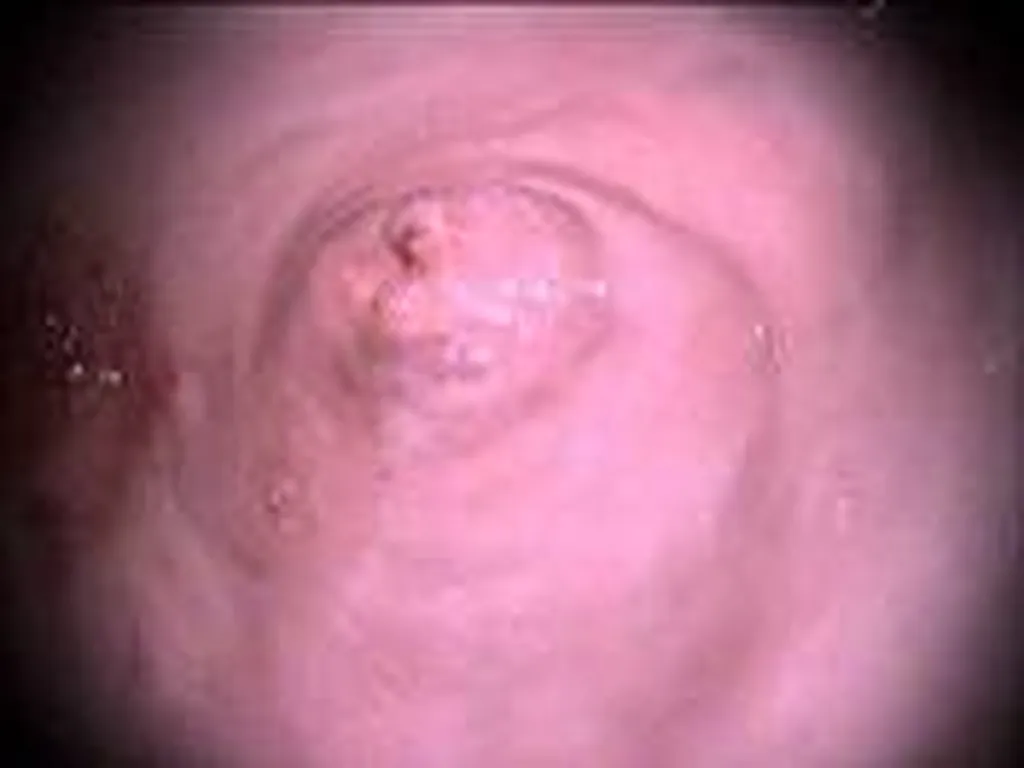

Affection touchant le système digestif (oesophagoscopie, gastroscopie, duodenoscopie, coloscopie) : corps étranger, mega-œsophage, gastrite aigue ou chronique, colite.

Des clichés sont effectués tout au long de l’intervention afin que vous puissiez visualiser les affections notées au cours de l’examen.